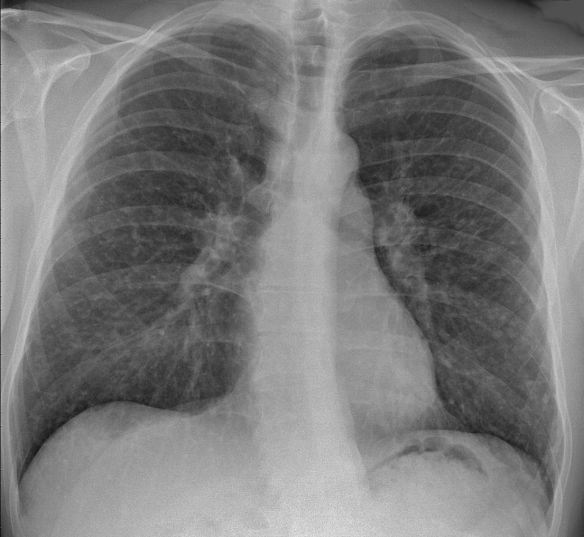

Sarcoidose is een zeldzame ziekte met ongekende oorzaak waarbij, door “onbekende” oorzaken ontstekingen ontstaan. Dat betekent voor mij veel onderzoeken en medicatie: kortademigheid in longen, pijn spieren, gewrichten en gramulomen in mijn longen. Veel ziekenhuisafspraken, medicatie, intraveneus infuus, pillen en de vele gezichten…..!

Longen van een Sarcoidose patient

Foto 1 en 2 voor diagnose Man Made Fibers – Foto 3 Het vermijden van rokers en Man Made Fibers